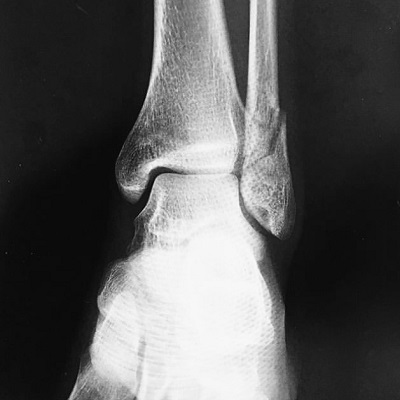

左遠位端骨折抜釘手術

今年1月に左足首を骨折した際に

2×4金物のようなものを足首に埋込み、

離れた骨を繋げる手術をしたのですが、

その2×4金物のようなものを取除く手術をしました。

それまで約10ヶ月間左足首に違和感がありましたが、

取除いたことでとてもスッキリしてます。

何よりも手術をして翌日にはしっかり杖なしで

立つことができたということに感動を覚えました。

そして大怪我を負ったことで

健康であることが素晴らしい。